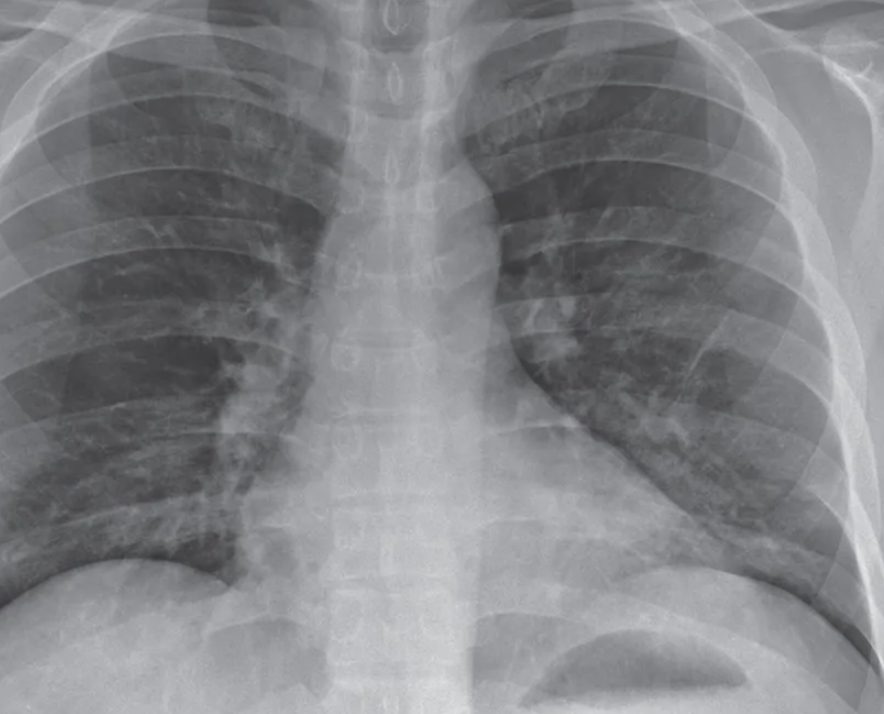

В Узбекистане за сутки 11 ноября зафиксировали 8 новых случаев заражения пневмонии. Общее количество заболевших достигло 27 651, сообщает Минздрав.

Выздоровевших пациентов — 18, общее их число достигло 26 163 человек.На данный момент больных пациентов — 1 488.